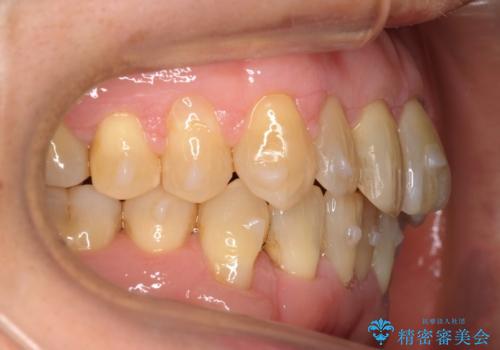

- 前歯のがたつきを主訴に来院。

右下の犬歯が歯ぐきが痩せて、歯肉退縮しておりそれを抜歯しました。

上の前歯はIPRを行なっています。

右下の犬歯の1本抜歯で最小限の抜歯で並べることができました。

奥歯も上下交互になるようにかみ合わせることができました。